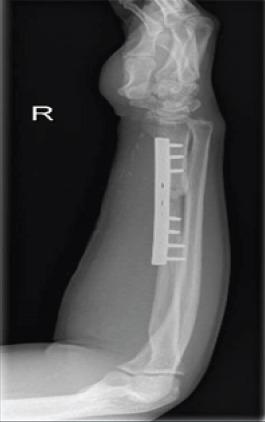

慢性盖氏骨折脱位:一例报告

Chronic Galeazzi Fracture-Dislocation: A Case Report.

Galeazzi fracture-dislocation is a unique entity of forearm fractures since they involve a fracture of the radius shaft, along with the dislocation of the distal radioulnar joint, the gold standard of treatment for adults is open reduction and internal fixation with or without repair or pinning of the DRUJ.

CASE REPORT

We present a case of a 27-year-old male with a neglected Galeazzi fracture for over 2 months, the patient was treated with open reduction and internal fixation without the need of a salvage procedure and achieved excellent outcomes.

盖氏骨折脱位是前臂骨折中的一种独特类型,因为它涉及桡骨干骨折以及下尺桡关节脱位,成人治疗的金标准是切开复位内固定,可选择修复或固定下尺桡关节,也可不进行修复或固定。

病例报告

我们报告一例27岁男性,其盖氏骨折被漏诊超过2个月,该患者接受了切开复位内固定治疗,无需补救手术,取得了良好的治疗效果。